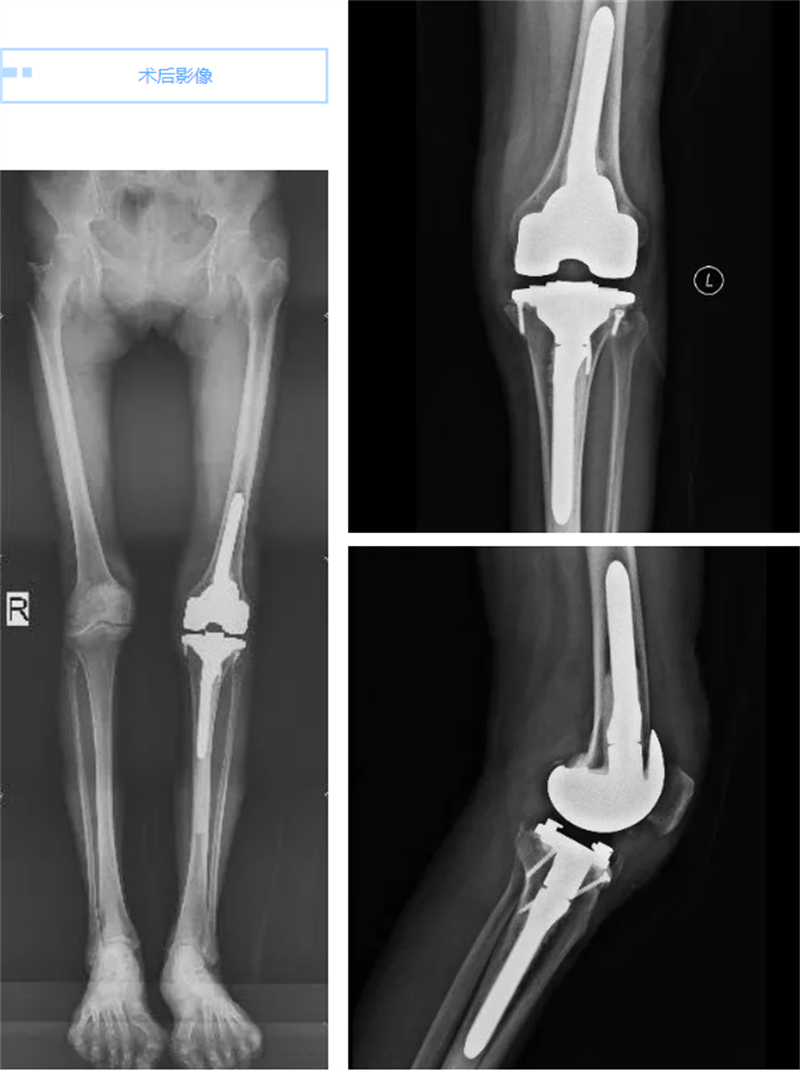

手術過程雖然復雜且技術難度極大,但在關節骨病科專家團隊的精心操作下,手術順利完成。術后當天,當莫女士看到自己的左膝關節重新變直時,她幾乎不敢相信自己的眼睛。次日,當她嘗試著下地走路時,發現膝關節竟然不再疼痛了,想到出院后能跟姐妹們一起跳廣場舞,莫女士笑得合不攏嘴,她仿佛重獲了新生,對未來充滿了期待。周圍的病友們也紛紛向莫女士送上了祝福,夸贊她仿佛重回了“18歲”。

在關節骨病科團隊的精心治療和護理下,莫女士的康復進展順利,她不僅恢復了健康,更重要的是,她找回了對生活的熱愛和信心。相信在不久的將來,就能在廣場上看到莫女士翩翩起舞的身影,盡情享受著美好生活。